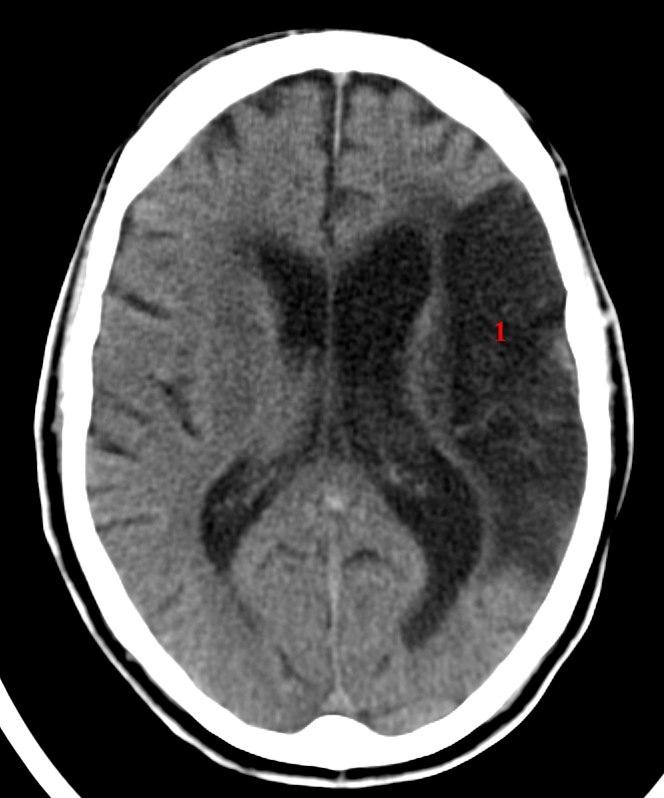

Cerebralt infarkt media

CT axialbilde uten kontrast

Stort infarkt i arteria cerebri medias forsyningsområde på pasientens venstre side (1). Infarktet er ikke helt ferskt.